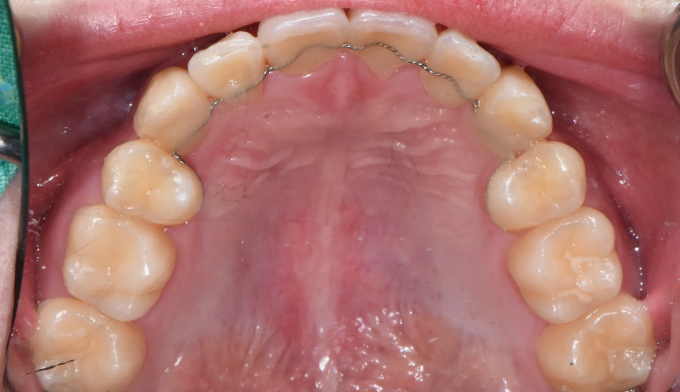

이가 배열될 공간이 부족해서 삐뚤빼뚤하게 나왔습니다.

돌출형인 얼굴을 고려하여도 어차피 발치교정이 필요할것 같아서 성인이 된 이후에 치료할것을 권유하였습니다.

하지만 본인 스스로가 고르지 못한 앞니에 컴플렉스를 가지고 있었고, 어차피 교정할거면 빨리 진행하길 원했습니다.

총 치료기간은 19개월 입니다.